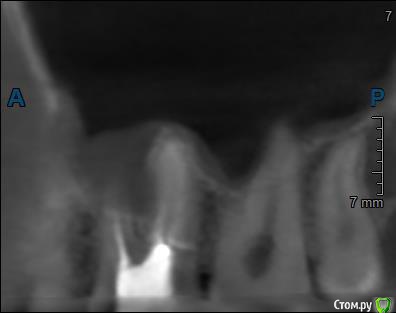

Здравствуйте! Верхний правый шестой зуб пломбировали 3 месяца назад. Примерно месяц назад он начал ныть, после насморка, сначала периодами, а теперь почти постоянно. При постукивание (ощущается не совсем так, как другие зубы) и пальпации десны он не болит. 2,5 месяца назад удаляли кисту из гайморовой пазухи. Может ли быть это какое-то воспаление и есть ли вероятность устранить его какими-нибудь антибиотиками, если да, то как, или может удалить зуб? Если есть воспаление, то какие могут быть последствия если не удалить зуб?

(Снимки с КТ, первые 8(Image) - сделаны сейчас,по 4 в разных проекциях, вторые 8(Before) - сделаны 5 месяцев назад до удаление кисты и повторного пломбирование зуба( до повторного пломбирование он реагировал на горячее, был запломбирован 3 года))

переличили зуб адекватно, во всяком случае по снимкам